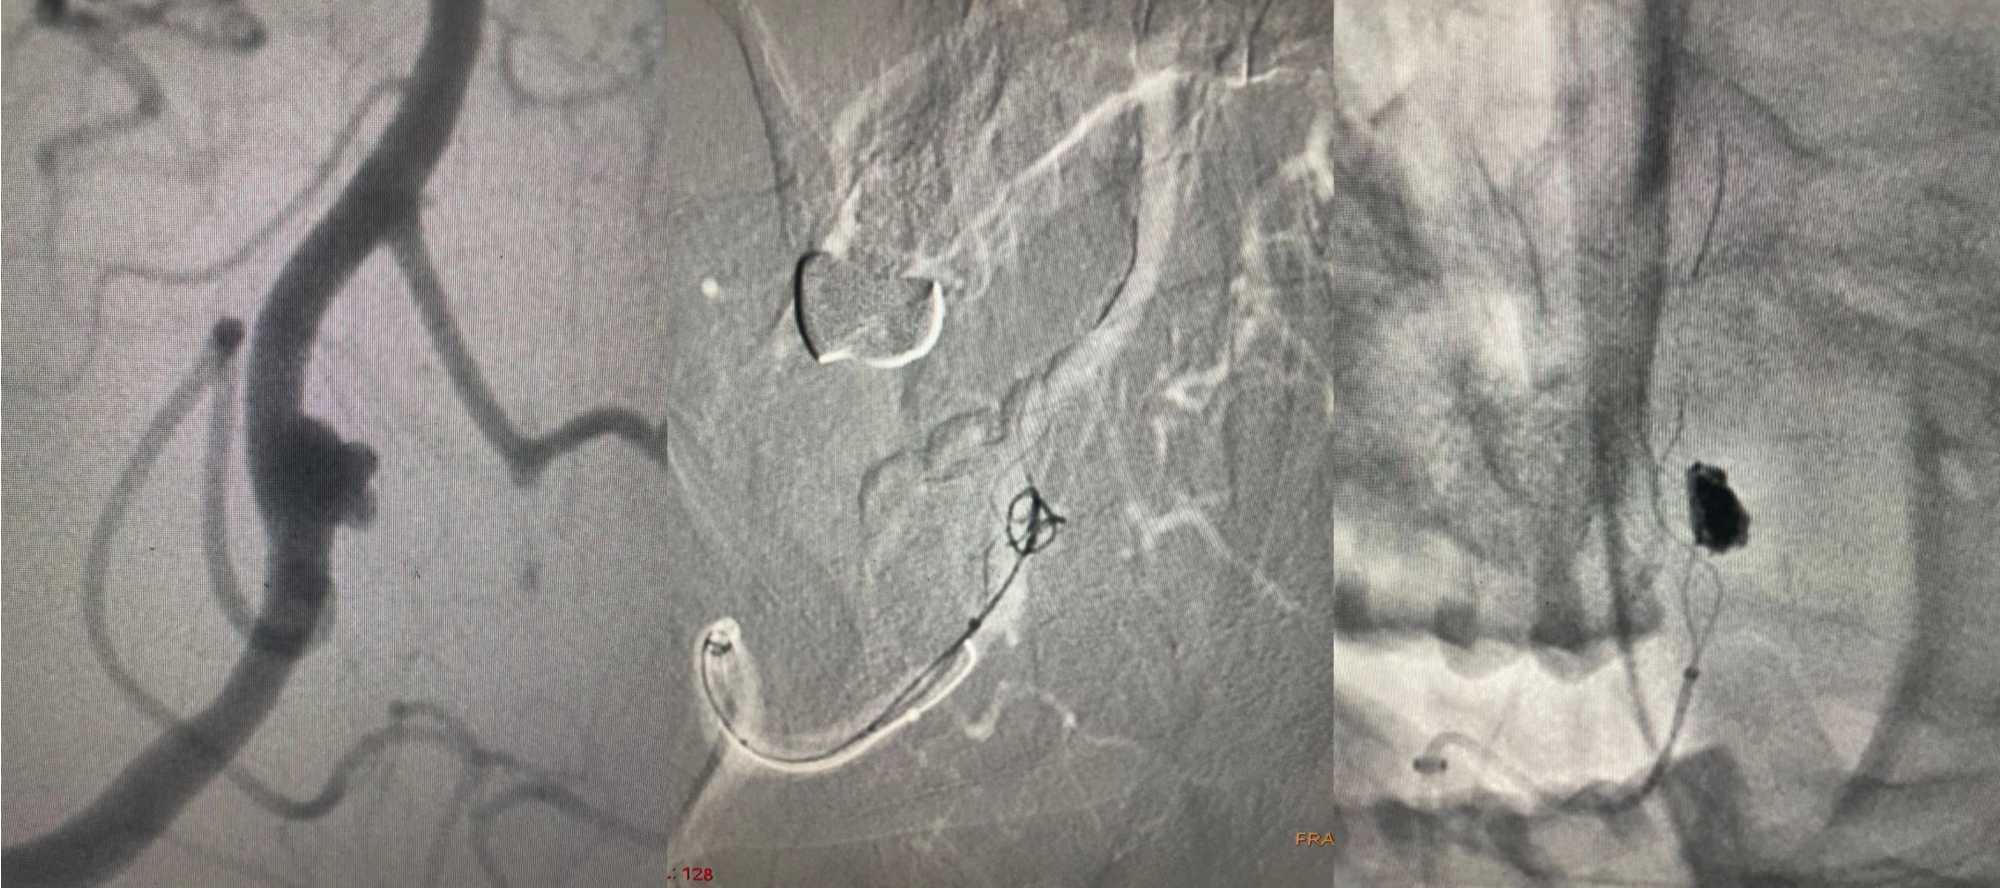

颅内动脉瘤的介入治疗:支架辅助弹簧圈栓塞颅内动脉瘤

颅内血管狭窄:介入治疗,球囊扩张后支架置入